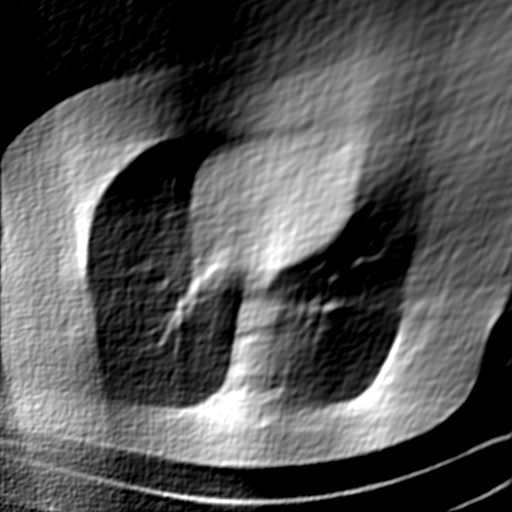

Fig. 4 presents the reconstruction results and residual images obtained by different methods for limited-angle reconstruction. As can be seen, the learning-based methods outperform the direct method and TV model, which exhibit serious artifacts in the missing angle region. Although the denoiser introduced by the FBP-Unet can somehow deal with the noises, the result still presents obvious artifacts. Compared to the SIPID, PD-net and FSR-nets, our LRIP-net1/2 can better preserve the image details and edges with less information left in the residual images. Thus, both the quantitative and qualitative results confirm that the low-to-high double-resolution strategy can improve the reconstruction accuracy for the limited-angle reconstruction problem.

We observe that the low-resolution image prior plays an important role in our method. More specifically, we compare the results of our LRIP-net with respect to different low-resolution priors, which are obtained by down-sampling rate of 1/2, 1/4, and 1/8, respectively. As can be seen in Table III, the best reconstruction results are obtained with the image prior reconstructed by the down-sampling rate of for 150∘, 120∘ and 90∘ limited-angle reconstruction. The visual comparison based on different image priors are also provided in Fig. 5, where obviously less artifacts are left in the reconstruction image by LRIP-net1/8. By comparing the running time, it is easy to see that the smaller the low-resolution image prior, the faster the LRIP-net works.